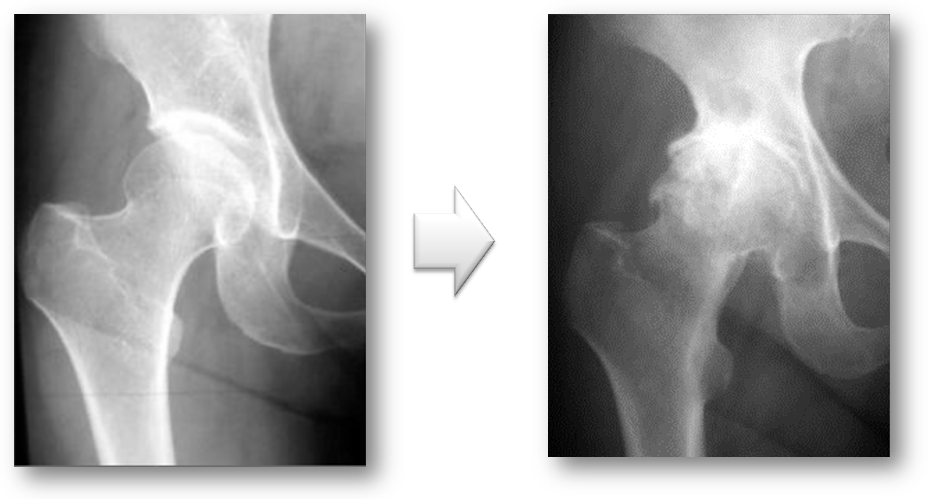

4. 変形性股関節症

変形性股関節症には、一次性と二次性があります。一次性は、長い年月を経てあるいは関節の使いすぎによって軟骨が消耗して起こります。二次性は、乳児期の股関節の脱臼や発育不全などの臼蓋形成不全によって早期から起こる変形性股関節症です。

レントゲンで見ると一次性は、正常な股関節が長い年月や股関節の使い過ぎによって軟骨が消耗して変形性股関節症が発症します(図7)。二次性は、元々臼蓋形成不全により体重がかかる部分が限られており早期なら軟骨が消耗し変形性股関節症になります(図8)。

図7. 一次性の変形性股関節症

長い年月を経て、あるいは関節の使いすぎによって起こる。